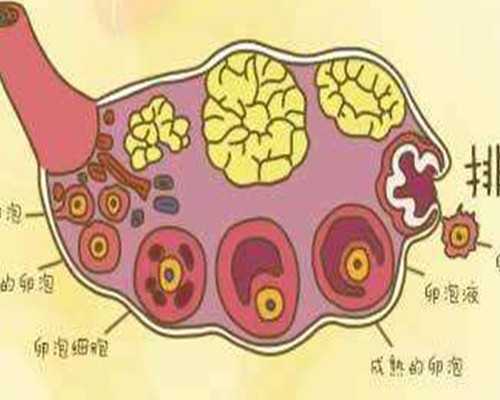

這當(dāng)中主要原因是卵子質(zhì)量與卵巢功能的退化而引起,再加上環(huán)境污染、輻射、化學(xué)品等多種不良因素影響,卵子質(zhì)量無時(shí)不刻的發(fā)生著退化與改變。

美國(guó)試管嬰兒恩西諾分院RobertBoostanfar[羅伯特布斯坦福]說:據(jù)多年臨床調(diào)查,卵巢的儲(chǔ)備功能在30-35歲以后便開始迅速下降。同時(shí),如果在35歲之前曾有多次懷孕流產(chǎn)、第一胎不健康經(jīng)歷,更會(huì)增加二胎風(fēng)險(xiǎn)和不孕不育的幾率。

? ? 對(duì)于高齡女性生育的困難,泰國(guó)試管嬰兒會(huì)根據(jù)高齡女性的身體情況制定適合的方案,合理促排,科學(xué)使用促排卵藥物控制性促排,減少對(duì)女性身體的傷害,這樣即使是高齡生育也不會(huì)對(duì)身體有太多的傷害,取得高質(zhì)量的卵子,增大試管嬰兒的成功率。在促排時(shí)會(huì)嚴(yán)格監(jiān)控和及時(shí)調(diào)整,在卵泡發(fā)育成熟及時(shí)取出,獲得多顆卵子,因?yàn)楦啐g生育的女性卵泡少,所以科學(xué)促排非常重要。